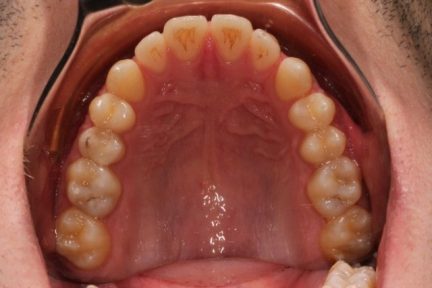

Classe III, articulé croisé antérieur, béance, espacement, diastème

État initial